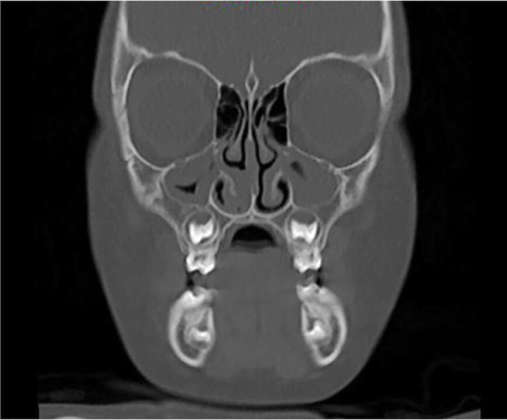

Tale studio permette di approfondire determinati aspetti morfologici predisponenti alle OSAS, come particolari caratteristiche occlusali e craniofacciali12, ipertrofia adenotonsillare, anchiloglossia, deglutizione atipica ecc. Per un completo studio del caso viene richiesta, infine, l’esecuzione delle seguenti radiografie: l’ortopantomografia, la teleradiografia in proiezione latero-laterale e, in particolari situazioni cliniche, la CBCT per uno studio più approfondito delle vie aeree superiori (Figura 3).